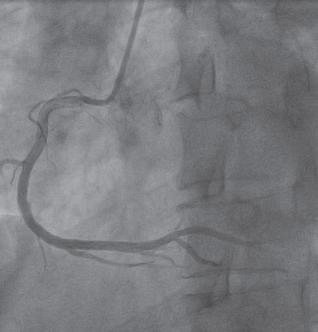

以桡骨茎突近端2cm可扪及桡动脉搏动处为进针点,常规消毒铺巾,用利多卡因逐层麻醉,显效后穿刺桡动脉,成功后常规置入6F桡动脉鞘,沿鞘管注入肝素钠注射液3000U、硝酸甘油200μg,在X线透视下,经鞘管送入直径0.035in(1in=2.54cm)、长260cm的超滑导丝,沿桡动脉、肱动脉、锁骨下动脉、主动脉弓到达升主动脉,再经导丝送入5F TIG导管至主动脉窦口,退出导丝,调整导管开口位置,分别在左、右冠状动脉开口与血管腔同轴后注入碘造影剂(图1-11、图1-1-2),血管显影后查看血管情况。造影完成后退出导管,桡动脉穿刺口予桡动脉止血器压迫止血,送患者安返病房。

图1-1-2 冠状动脉前降支造影